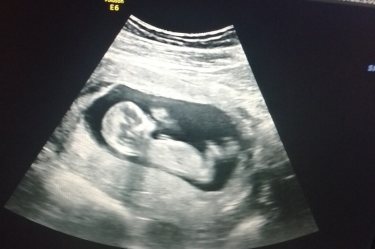

Мой скрининг 13 недель двойняшечки предположили мальчик и девочка, на фото мальчик.

Плоды большие их по одному фоткают оба в кадр невмещаются, а фото на бумаге 500р стоит я нестала покупать сфотографировала только того каторого последним рассматривали и оставили на экране)